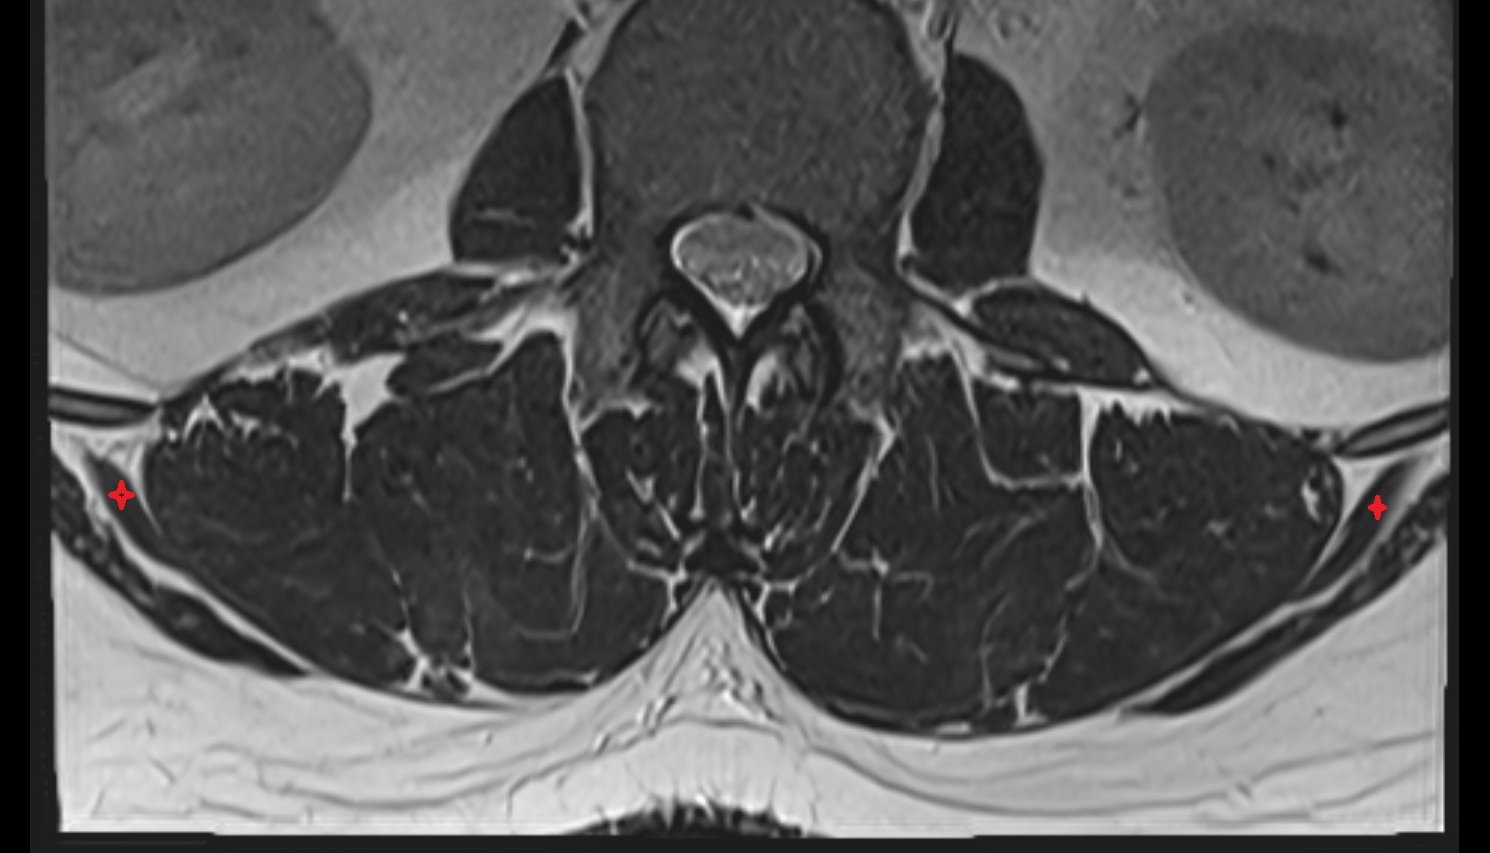

- Cauda equina

- Traversing nerve root of spinal nerve

- Exiting nerve root of spinal nerve